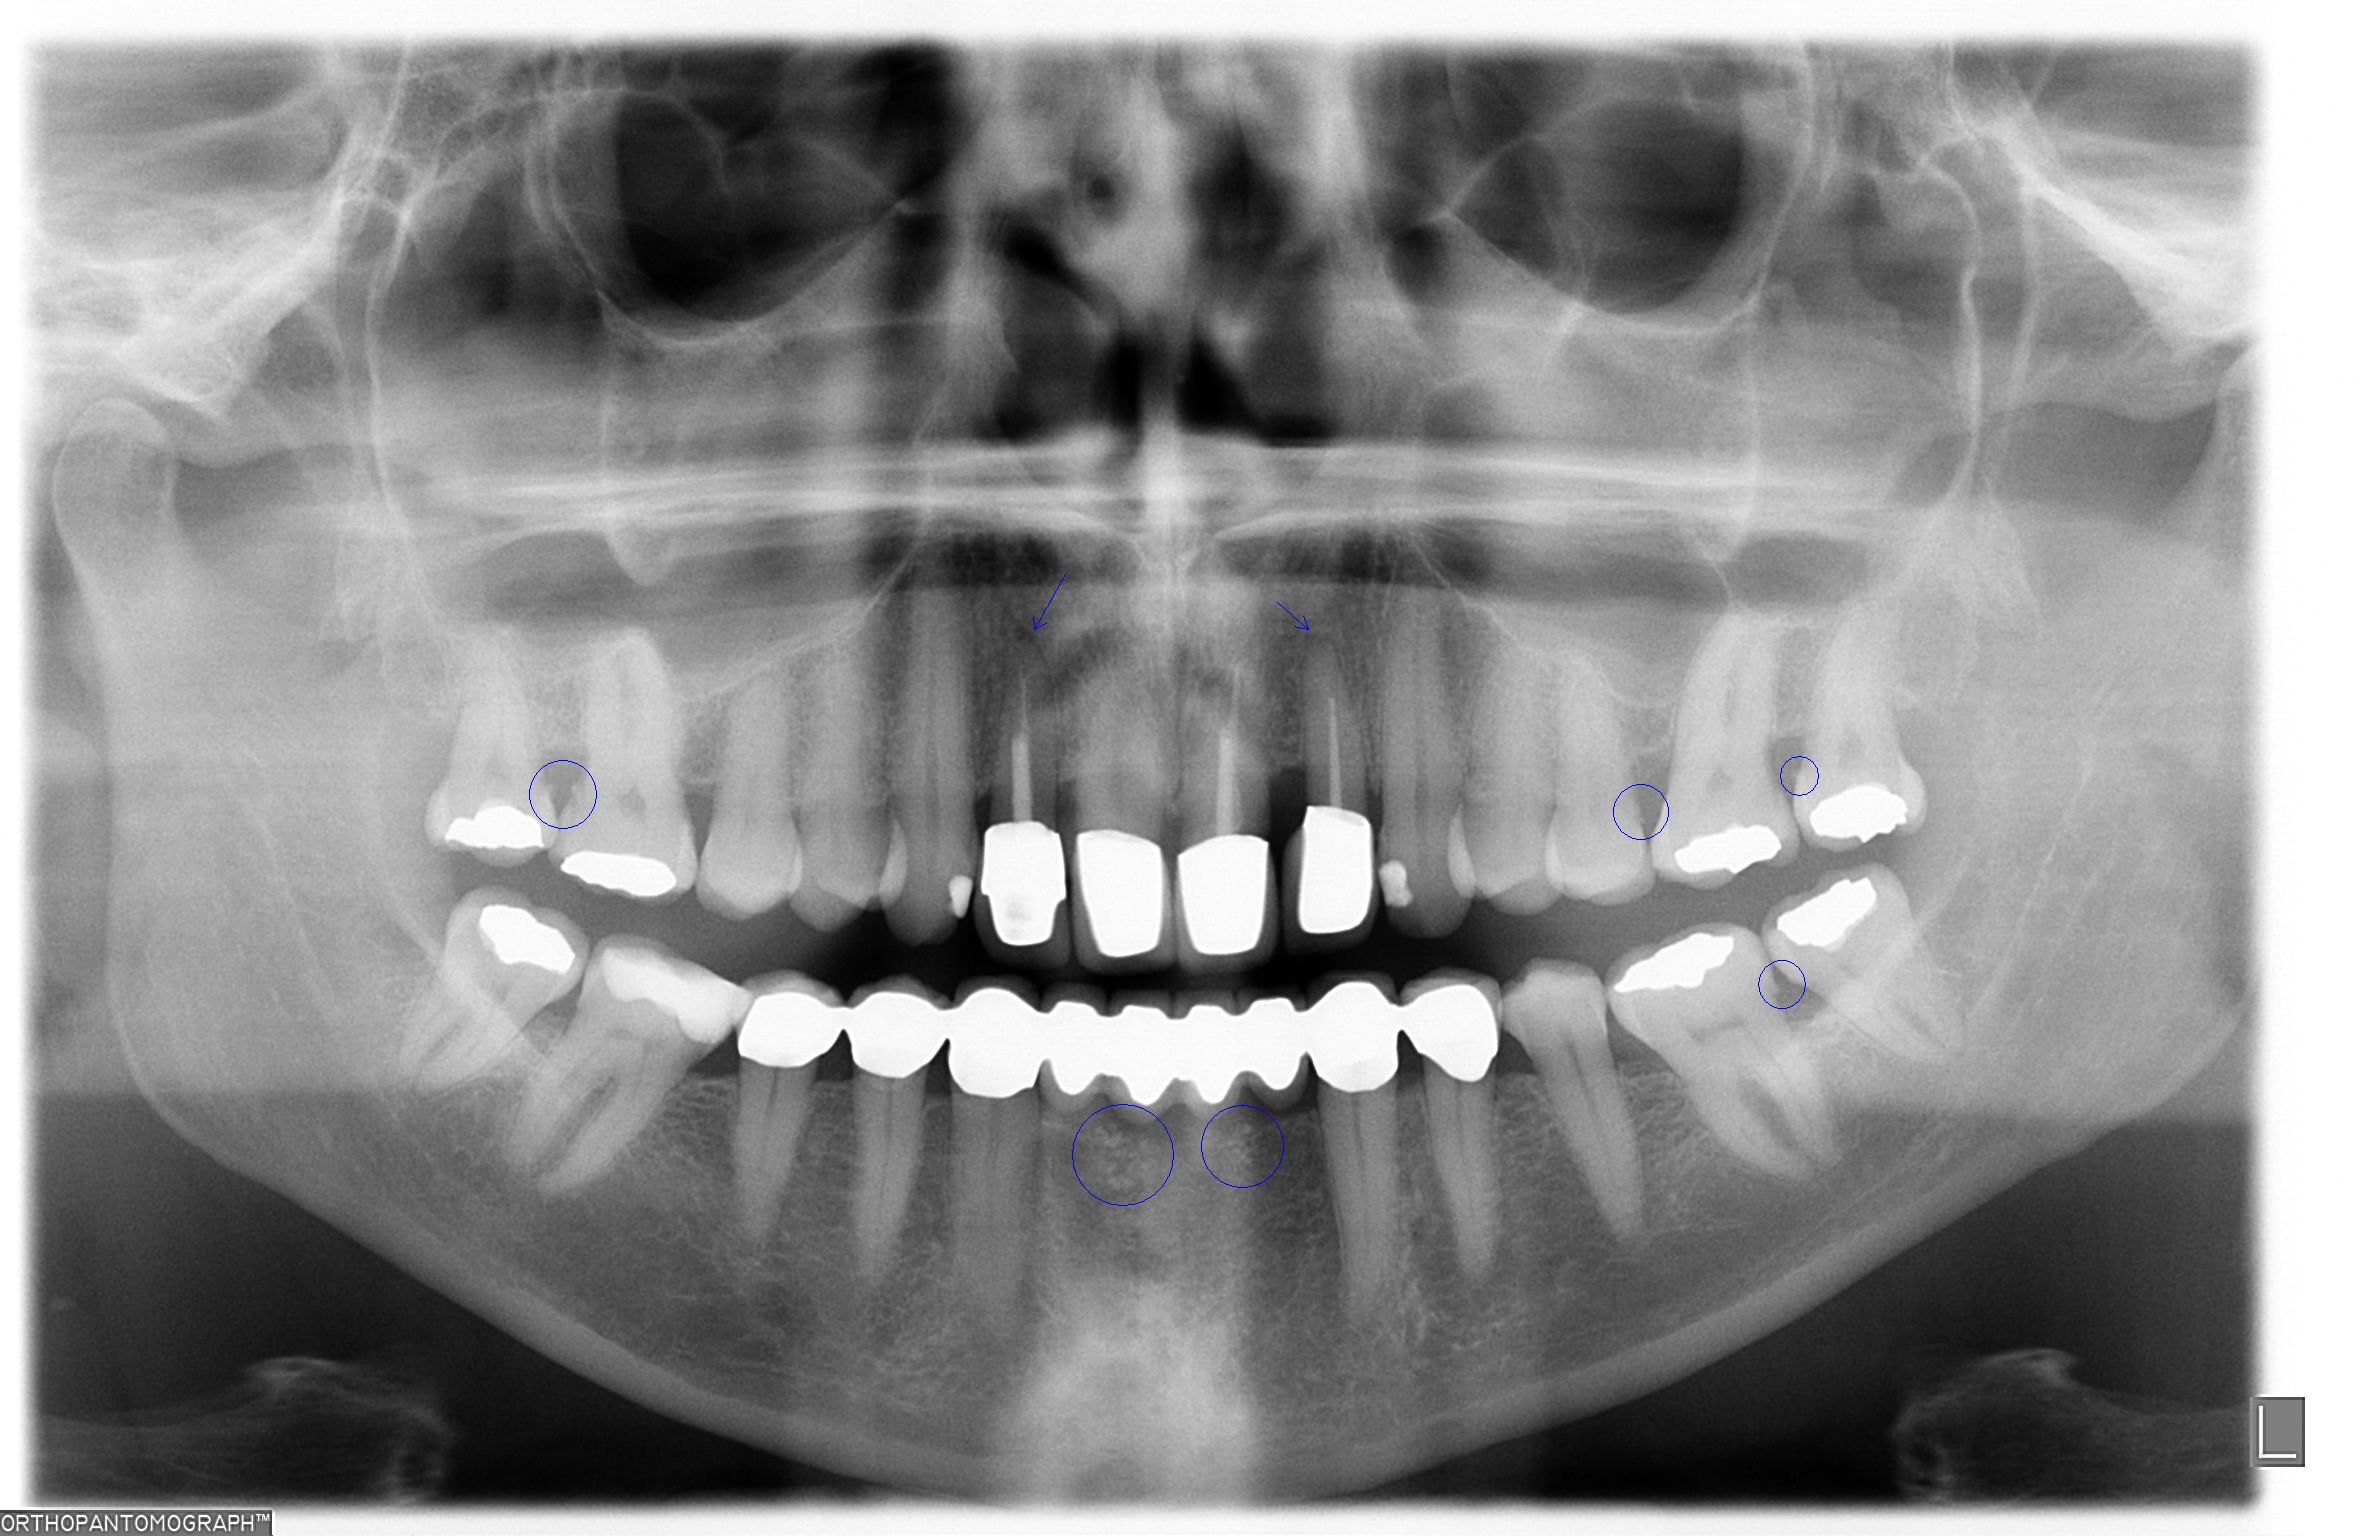

I. Befund des gesamten Gebisses / Behandlungsplan

Oberkiefer

11 KM kw kw KM 21

12 KM kw kw KM 22

13 PKM pw pw PKM 23

14 24

15 25

16 F2 c c F2 26

17 c F2 27

18 f f 28

Unterkiefer

48 f f 38

47 F2 c c F2 37

46 KM ww c F2 36

45 KM kw 35

44 KM kw kw KM 34

43 KM kw kw KM 33

42 SKM b b SKM 32

41 BM b b BM 31